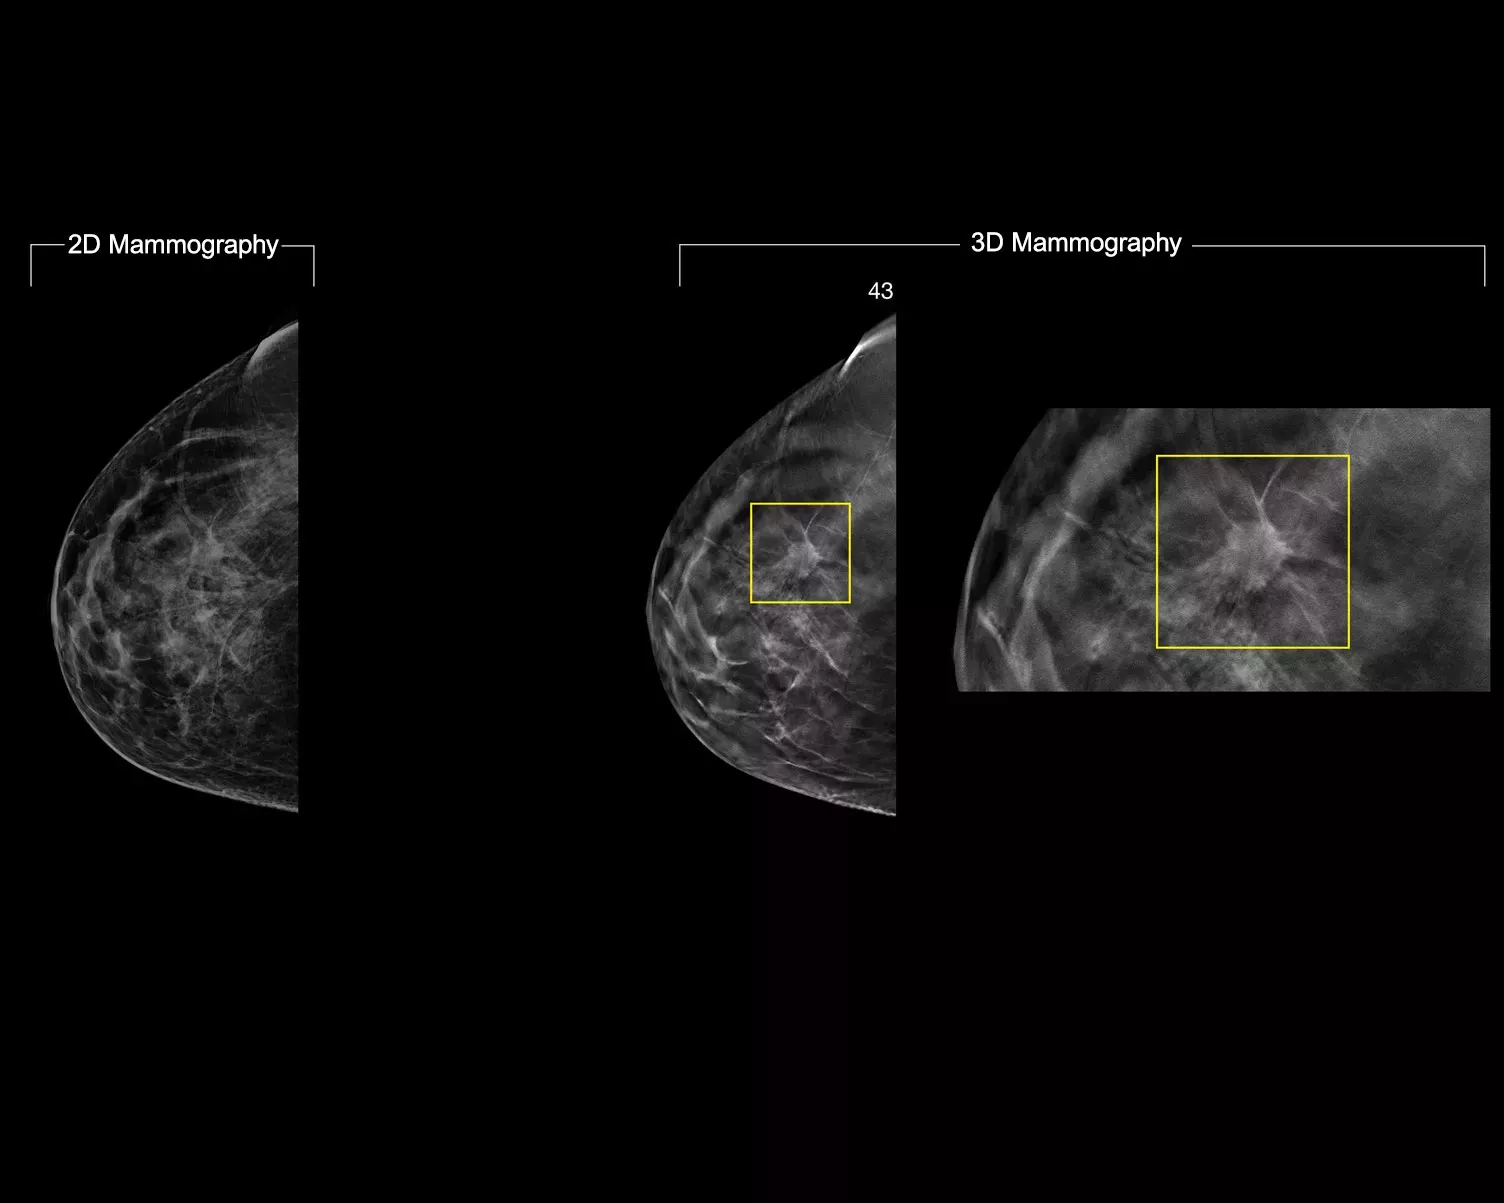

A machine-learning algorithm designed to aid radiologists' diagnostic performance in detecting breast cancer1-3 from tomosynthesis images obtained by using the Hologic Dimensions™ Mammography Systems. The algorithm locates lesions that are likely to represent breast cancer by searching each slice of the tomosynthesis image set. The suspicious areas are highlighted for concurrent reading at the radiologist's workstation to aid in interpretation.

Study shows +9% improvement in observed reader sensitivity for cancer cases.1.2 Works on standard and high-resolution tomosynthesis images; overlay on 3DQuorum SmartSlices and synthesised 2D images.

The algorithm looks for 3 main groups of suspicious lesions: calcifications, masses, densities and distortions, and any combination of these lesions. Outputs may vary on different reading workstations.